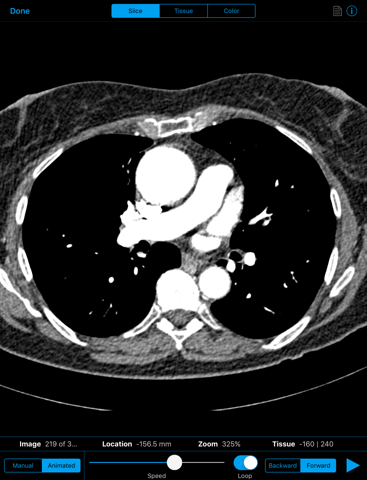

- 2D slice viewer offering manual or animated movement through dataset

- Multiple coloring schemes available in 2D and 3D modes